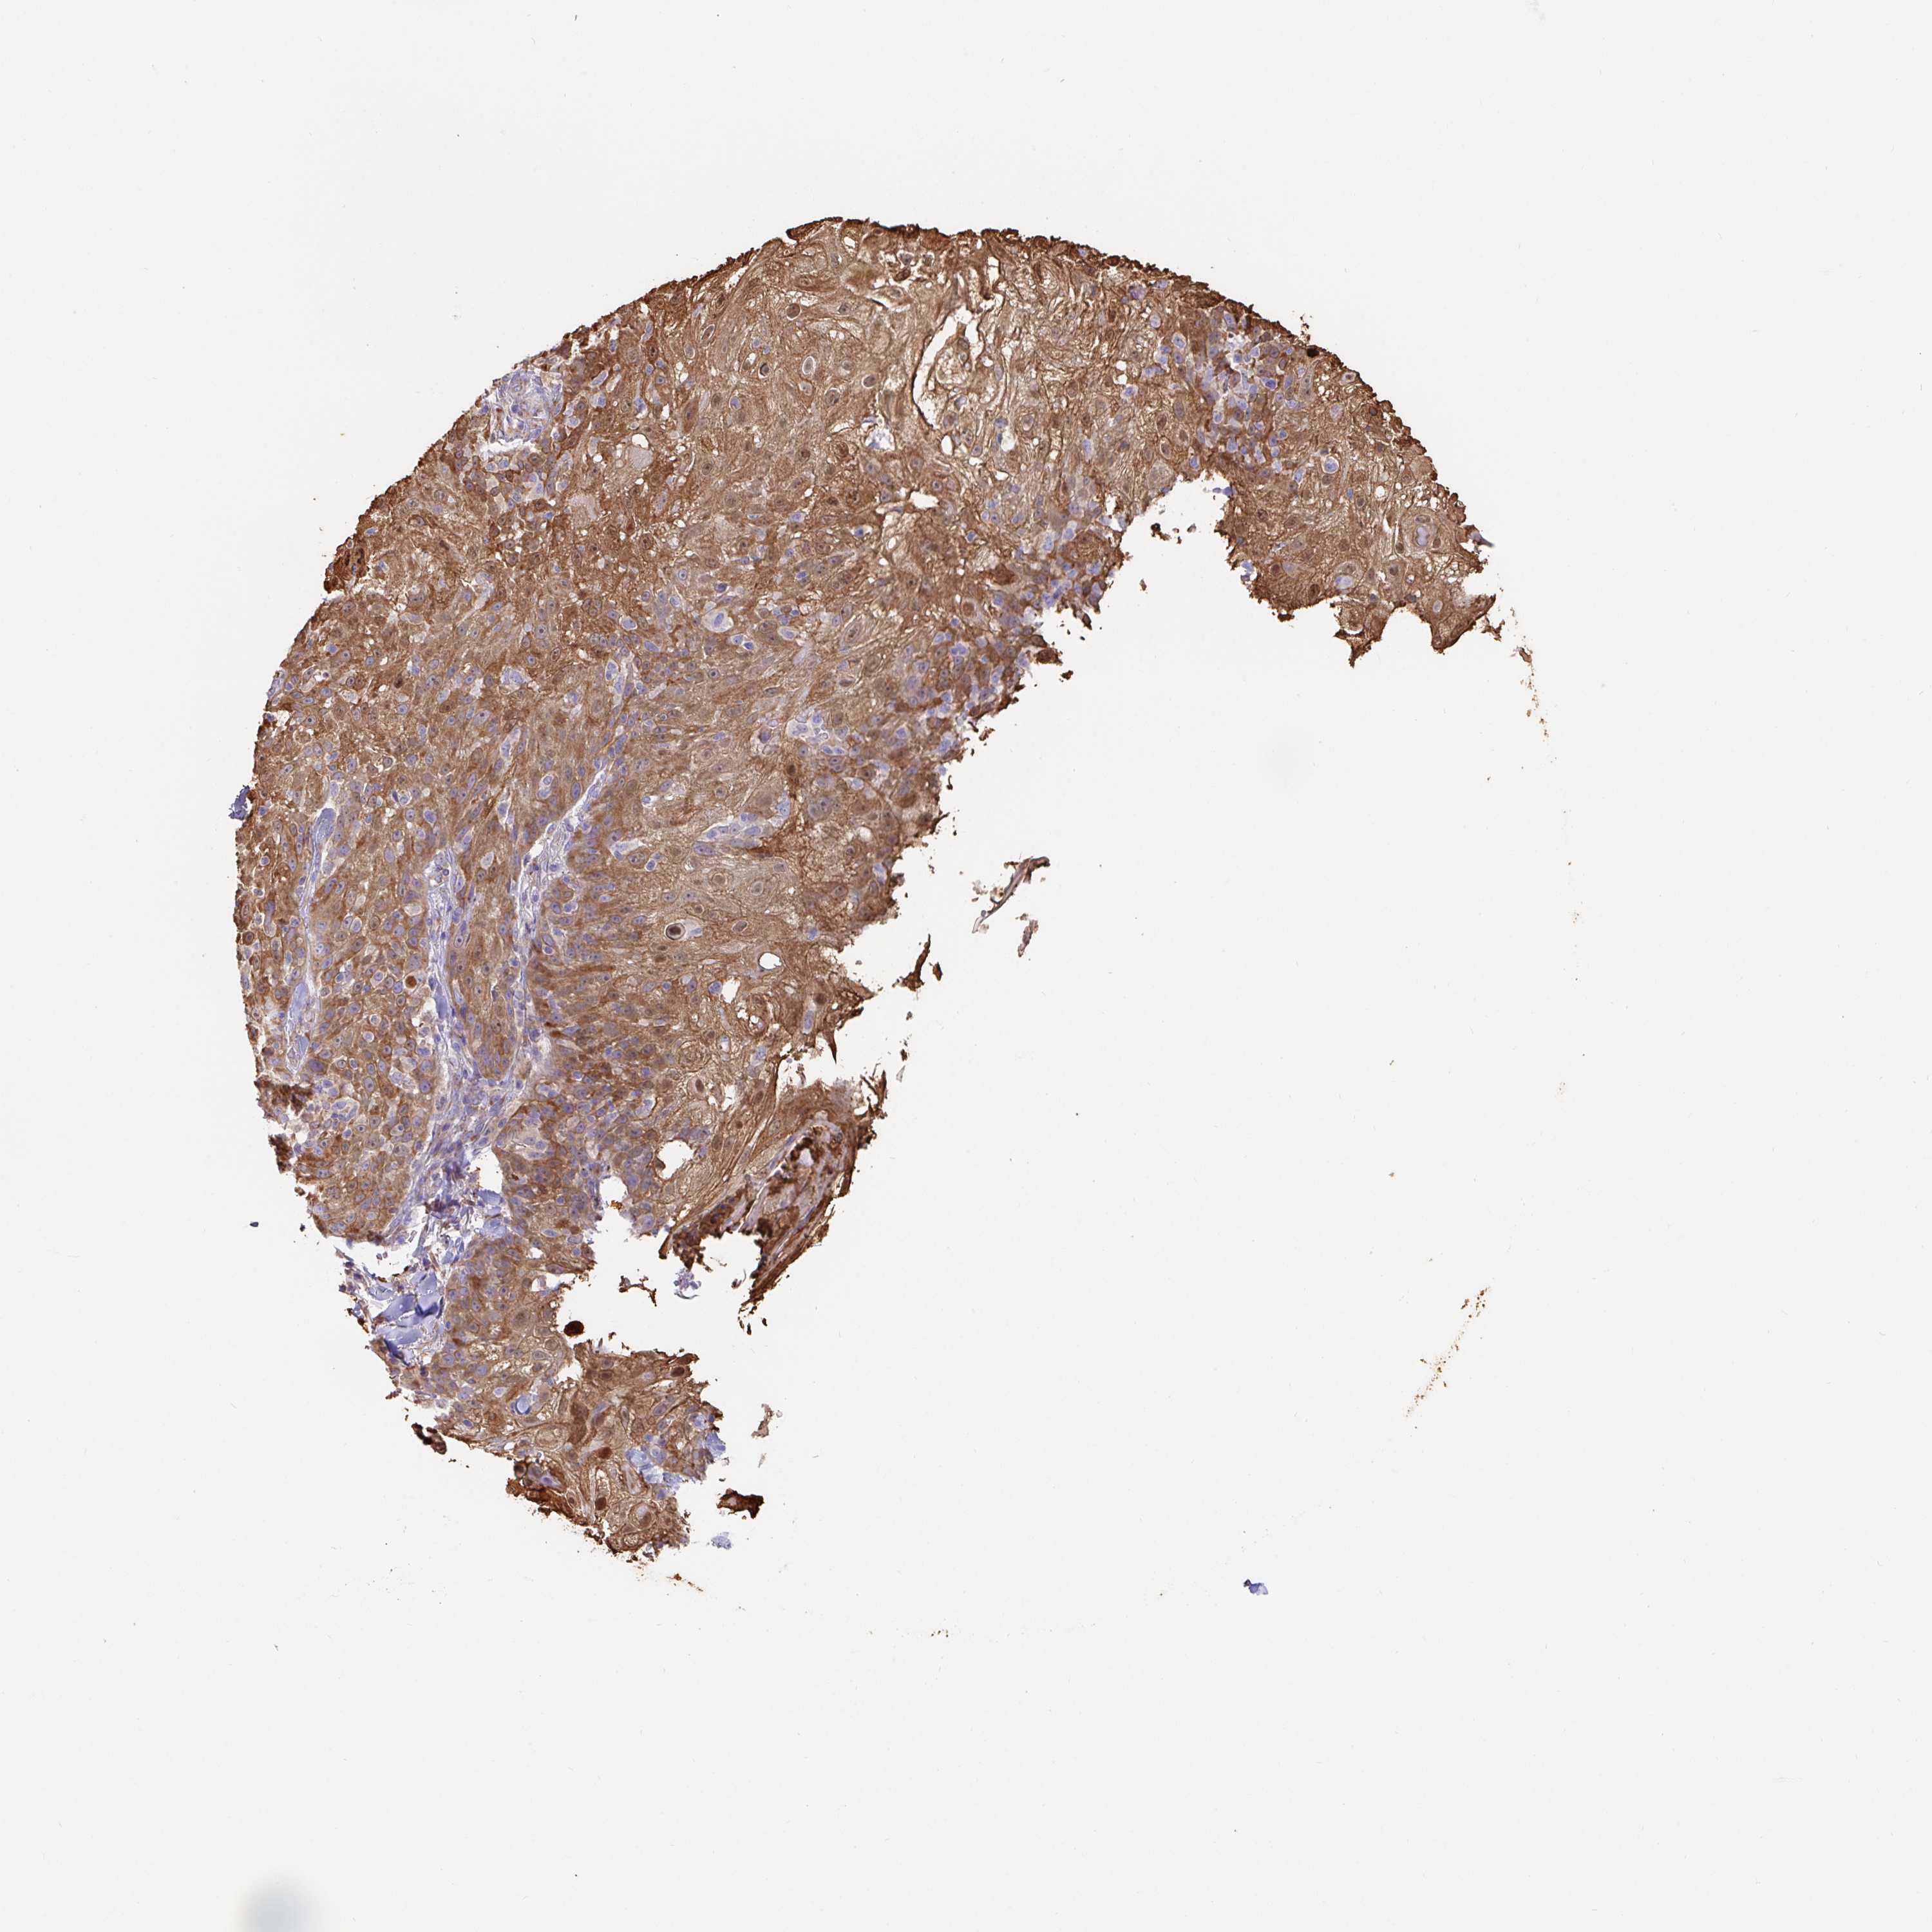

SKIN CANCER - Protein expressioni

A mouse-over function shows sample information and annotation data. Click on an image to view it in a full screen mode. Samples can be filtered based on level of antibody staining by selecting one or several of the following categories: high, medium, low and not detected. The assay and annotation is described here.

Antibody staining in the annotated cell types in the current human tissue is reported as not detected, low, medium, or high, based on conventional immunohistochemistry profiling in selected tissues. This score is based on the combination of the staining intensity and fraction of stained cells.

Each image is clickable and will lead to virtual microscopy that enables deeper exploration of all samples and also displays staining intensity scores, fraction scores and subcellular localization as well as patient and tissue information for each sample.

Antibody HPA035199

Antibody CAB004272

Staining

High

Intensity

Strong

Quantity

>75%

Location

Cytoplasmic/membranous

Basal cell carcinoma

Squamous cell carcinoma, NOS